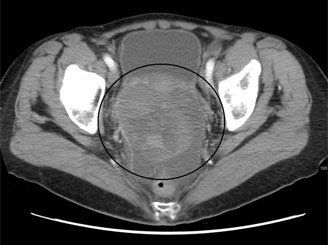

Ovarian cancer as seen on CT; source: James Heilman, MD